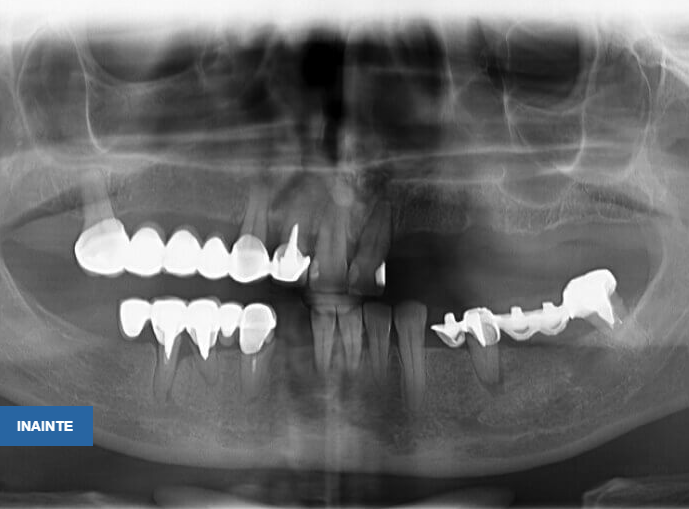

Pacienta în vârstă de 46 ani se prezintă în clinică având edentație uniterminală bimaxilară (maxilar 1 modificare, mandibulă 4 modificari) cu parodontopatie marginală cronică profundă, dinții prezentând mobilitate grad 3, o proteză mobilă parțial acrilică incorect adaptată campului edentat cauzând inflamația mucoaselor pe care se sprijinea, restaurări protetice fixe metalo-ceramice incorect adaptate, unele fixate provizoriu pe bonturi fracturate, reacții periapicale.